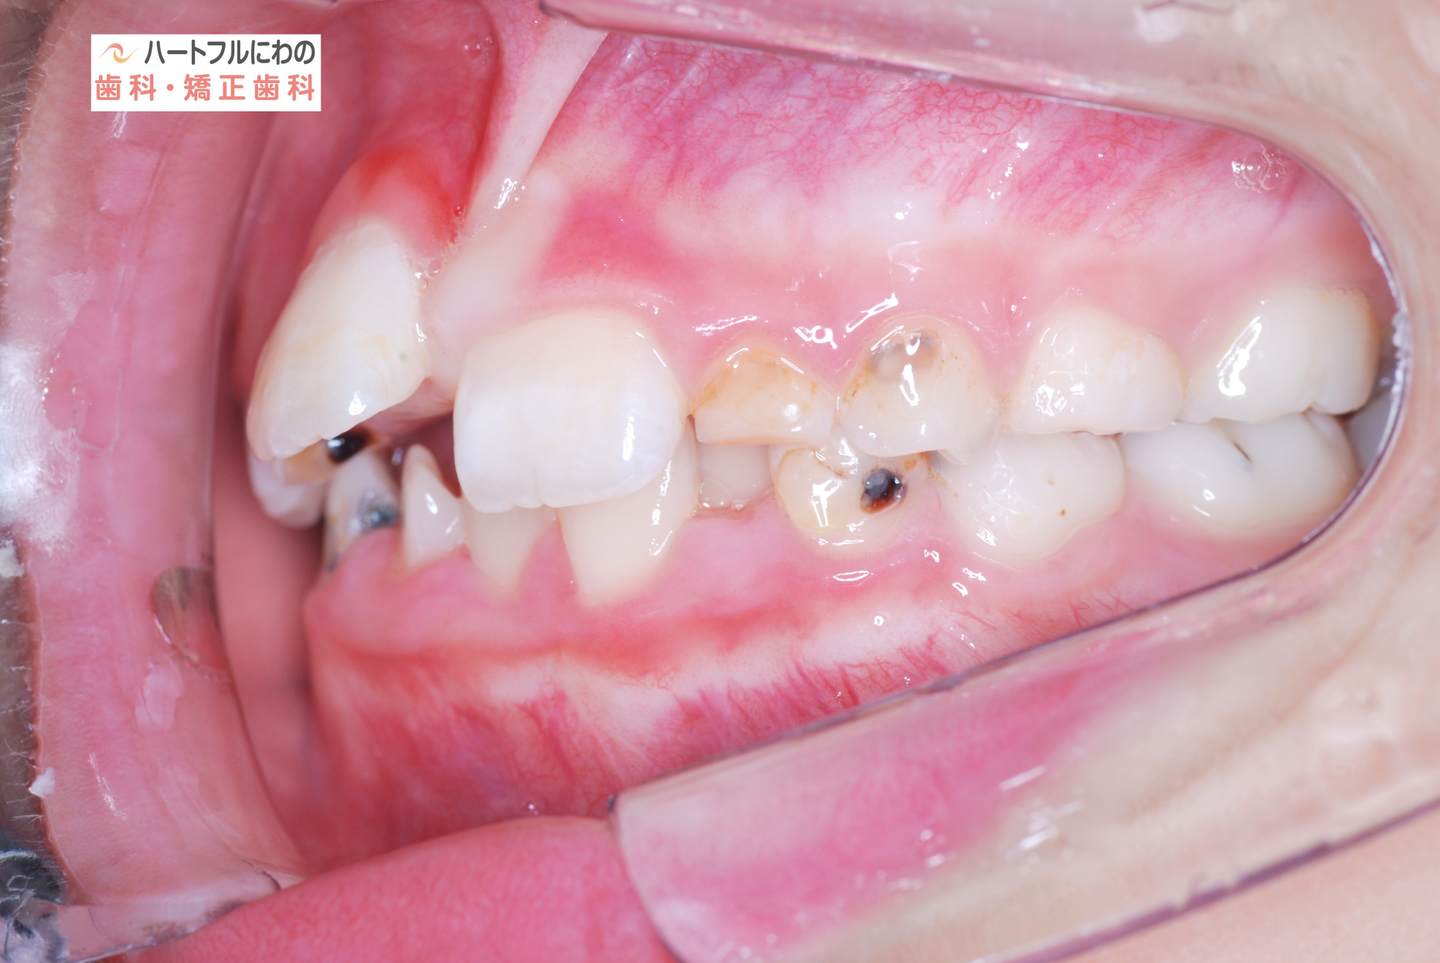

お口の中を拝見すると、上下の叢生(いわゆるガタガタ、乱ぐい)がみられ、多数の虫歯と歯肉炎がみられました。上唇小帯(上唇のすじ)の問題もありました。口呼吸で口腔内が乾燥すると通常の何倍も歯垢が付きやすくなり、虫歯や歯肉炎が頻発します。口呼吸の強い子は重なっている部分のかみ合わせが深い(下の歯がほとんどみえない)のもよく見られる特徴です。